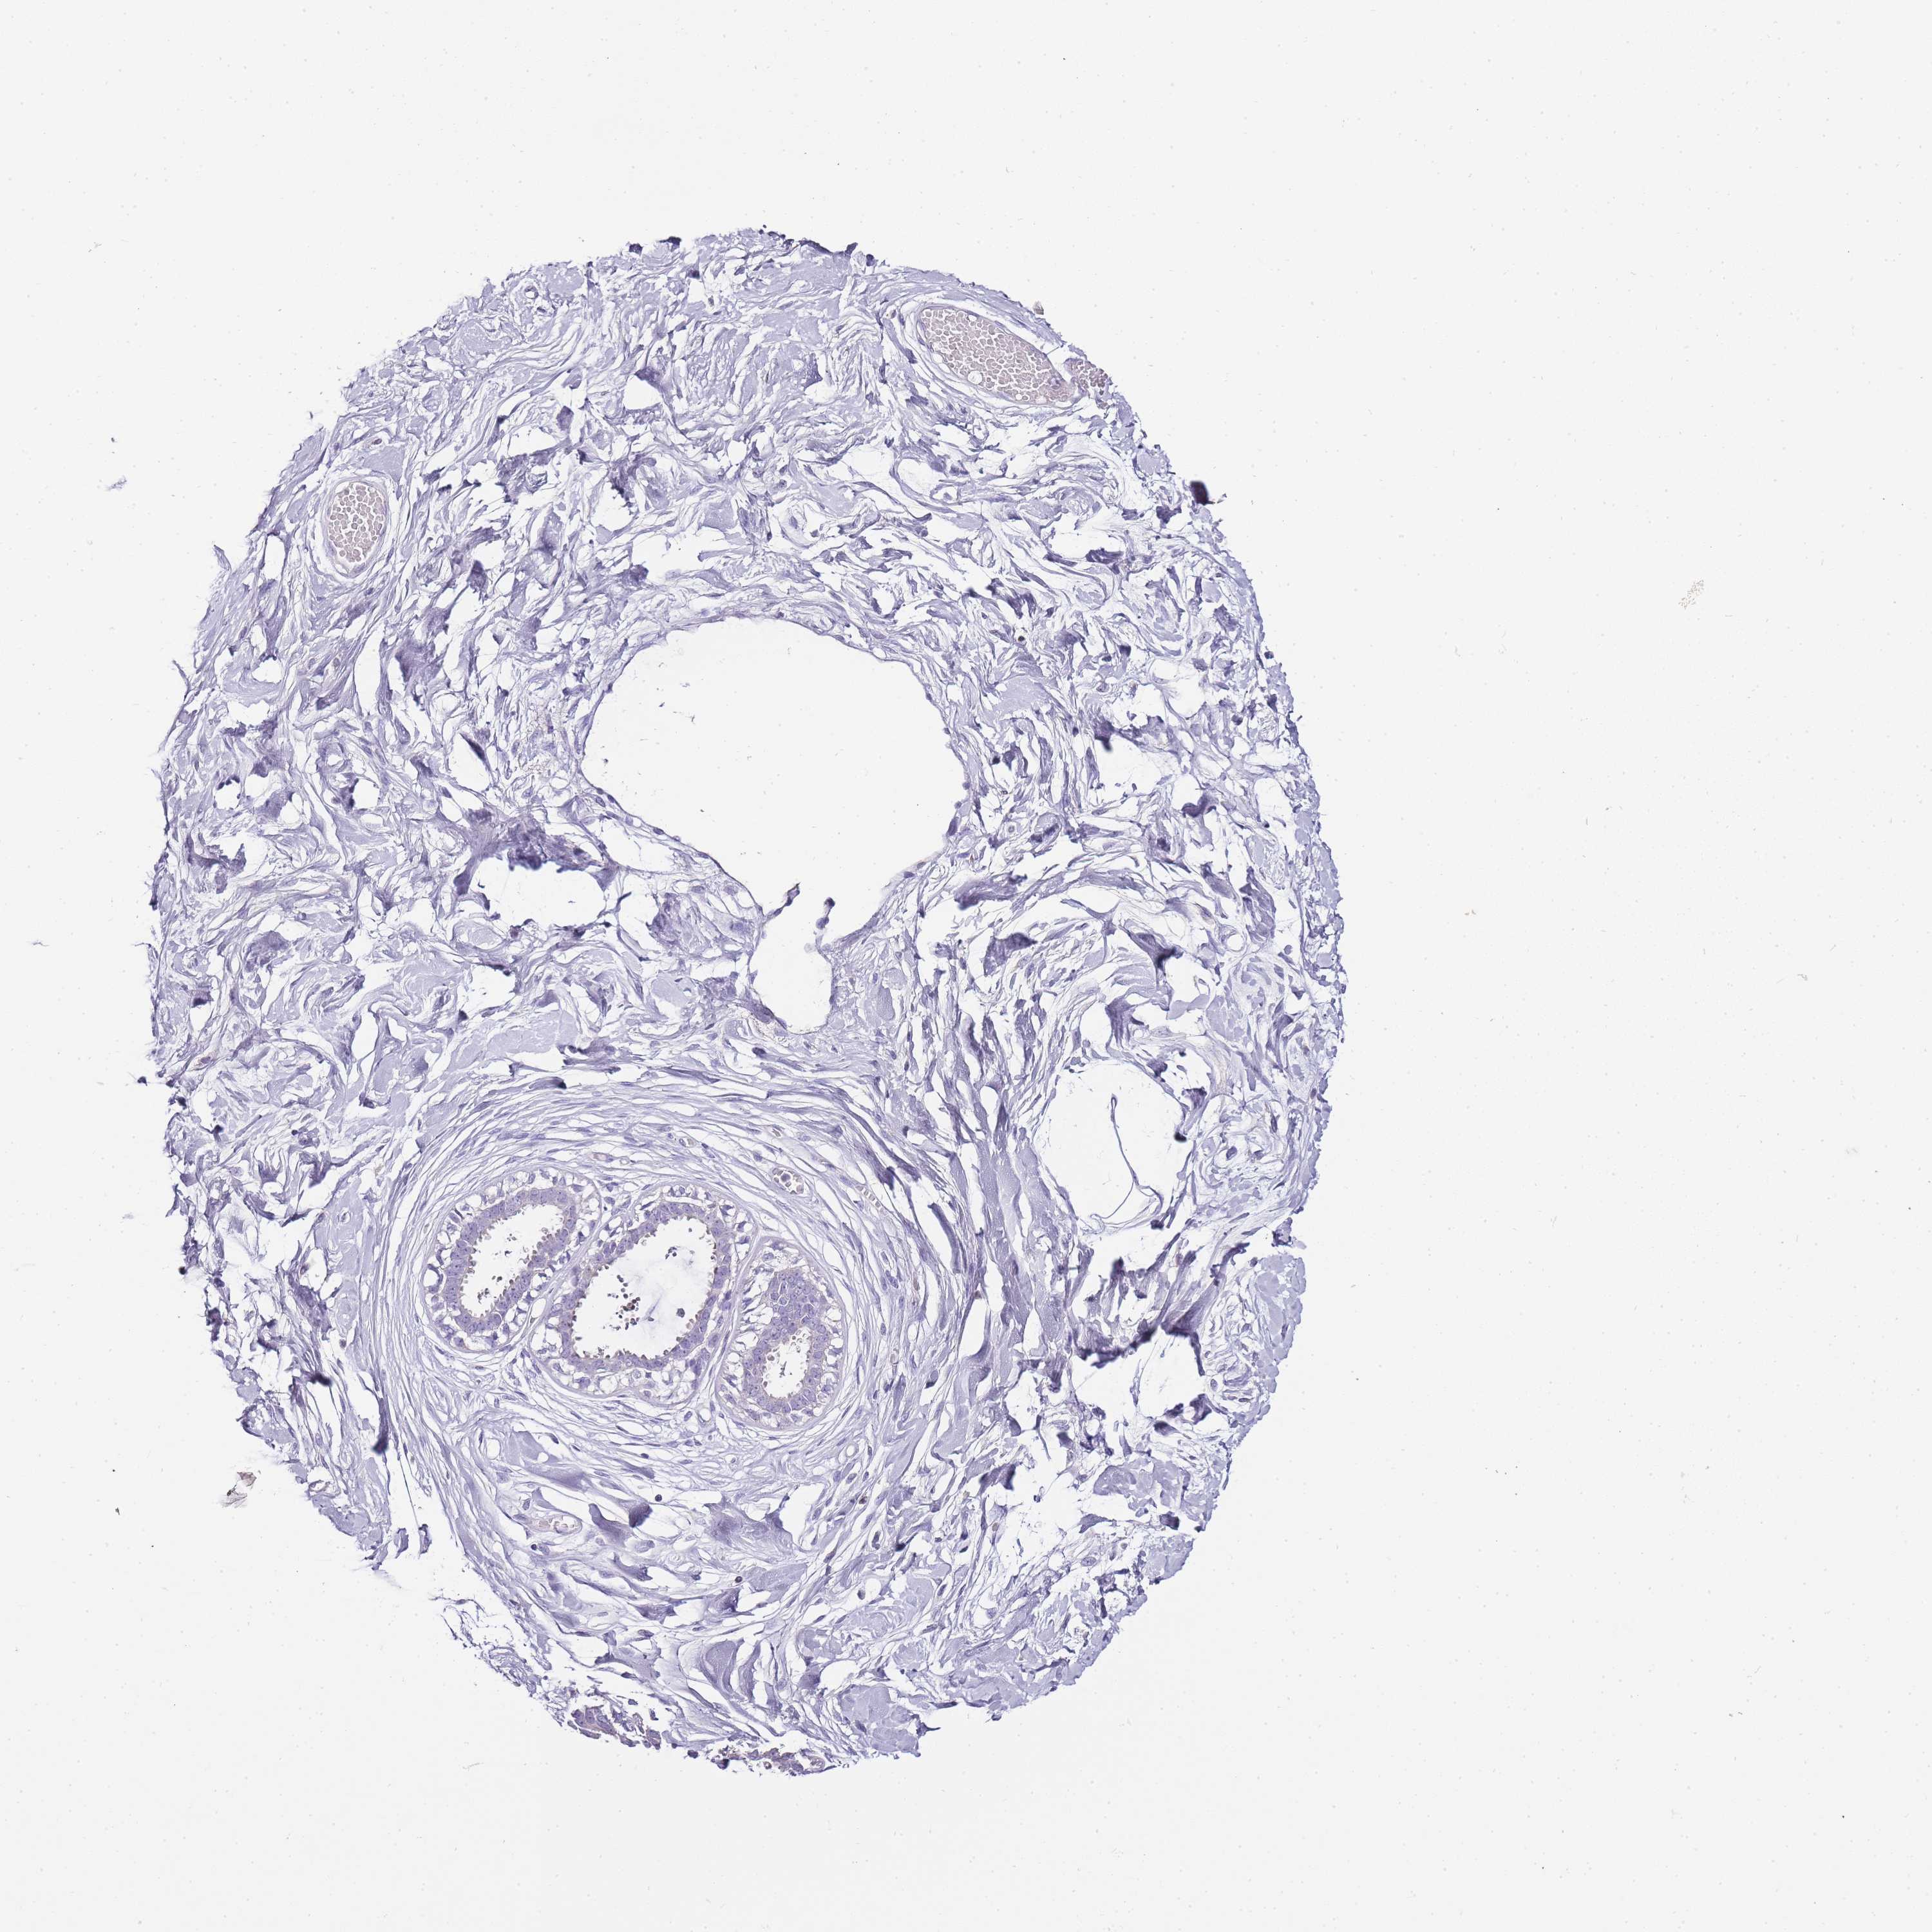

TISSUE PRIMARY DATA BREAST Show tissue menu

Breast

BREAST - Antibody stainingi

Antibody staining in the annotated cell types in the current human tissue is reported as not detected, low, medium, or high, based on conventional immunohistochemistry profiling in selected tissues. This score is based on the combination of the staining intensity and fraction of stained cells.

Each image is clickable and will lead to virtual microscopy that enables deeper exploration of all samples and also displays staining intensity scores, fraction scores and subcellular localization as well as patient and tissue information for each sample.

Antibody HPA041256

Adipocytes Not detected

Glandular cells Not detected

Myoepithelial cells Not detected